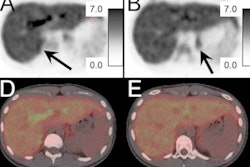

Mortensen's group sought to investigate the prevalence of CAC in patients with LDL-C levels of more than 190 mg/dl and whether the presence of calcium would affect heart attack, stroke, and death rates. The team conducted a study that included data from 23,143 symptomatic patients included in the Western Denmark Heart Registry who underwent coronary CT angiography between January 2008 and December 2017. Over four years of follow-up, 1,029 adverse cardiovascular events and deaths occurred.

Out of the total patient group, 46.3% of patients had no CAC and 53.7% had detectable plaque. Patients with cholesterol measures of at least 190 mg/dl had the lowest prevalence of CAC scores of 0 (46.2%), but of these, most (77.2%) had no coronary plaque at all.